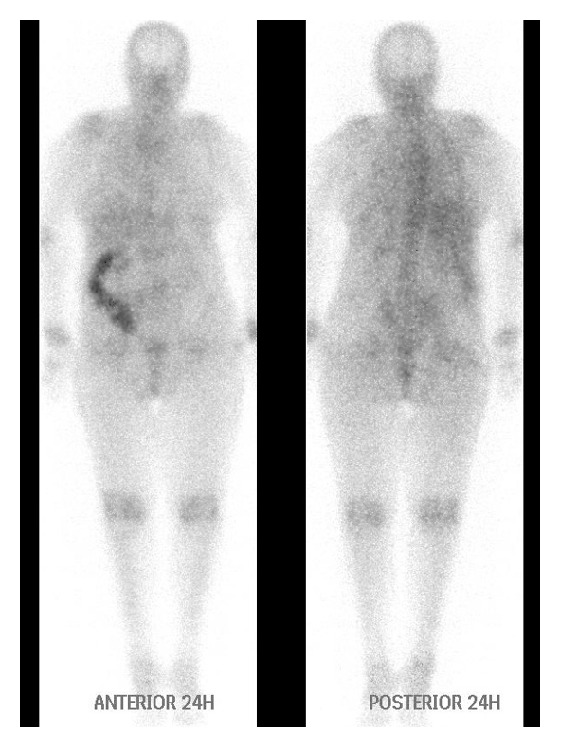

A few days later, the patient was readmitted for a blood transfusion and she was still febrile. The results of the immunologic tests were inconclusive {ANA (−), anti-ENA (+), and anti-RNP (+)}; the serum protein electrophoresis and the temporal artery biopsy were negative and so were the tests for the reactivation of the old TB infection. The patient was evaluated by a rheumatologist who recommended treatment with 20 mg of prednisone daily. After 21 days, the patient remained febrile and thus underwent a gallium-67 scintigraphy searching for a hidden focus of inflammation. The gallium-67 scintigraphy revealed persistent diffuse concentration of the gallium in the ascending colon (Figure 2) at 24-hour imaging, in discordance with the colonoscopy (no signs of active inflammation at the ascending colon).

Figure 2.

The gallium-67 scintigraphy revealed persistent diffuse concentration of the gallium in the ascending colon at 24-hour imaging. Gallium-67 excreted into the bowel and laxatives are essential for the differential diagnosis between true positive increased bowel activity and false positive uptake due to bowel content.

The gallium-67 diffuse uptake of the ascending colon remained stable at the repeated 48- and 72-hour imaging without any topographic change after the use of laxatives (Figure 3).

After the use of laxatives, the gallium-67 diffuse uptake of the ascending colon not only remained stable but rather strengthened without any topographic change at the repeated 72-hour imaging, indicating active inflammation.